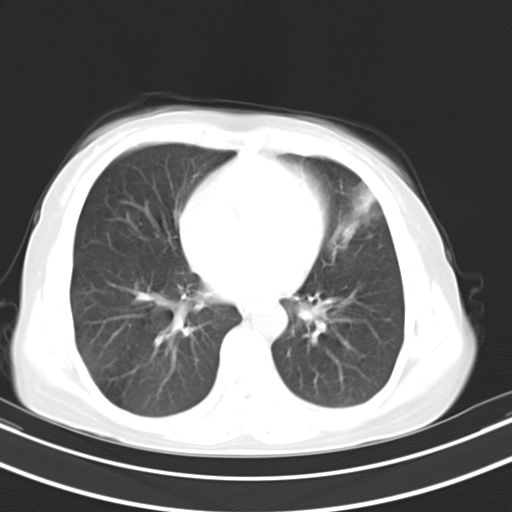

炎性灶;【1楔状实变影,有支气管气象,2近端纹理影增重】

右肺上叶尖后段班片影不能出外肺结核。左肺舌叶三角形实变影,增强明显。考虑炎性病变

右肺为炎性改变,左肺病灶影像所见1、楔状实变影,边缘呈刀切样,见支气管气象,2、近端纹理影增重。

并从一元化来解释,还是符合炎性病灶。建议抗炎后复查。

两肺病变考虑炎症可能性大。(左肺病变呈楔状实变影,有支气管气象,近端纹理影增重)。

1)右肺上叶前段及左肺上叶舌段感染性病变;建议抗炎治疗后复查。2)左侧少量胸腔积液。

考虑右肺上叶前段及左肺舌叶炎症,建议抗炎治疗后复查除外结核。

左肺舌叶病灶呈扇形分布,其内可见支气管影,胸膜面光滑,不支持肿瘤病变。